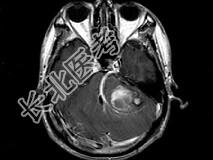

- 单项选择题男,45岁, 反复呕吐近1个月,加重5天, 根据所提供图像,最可能的诊断是 ( )

A、海绵状血管瘤

B、静脉血管畸形

C、脑出血

D、动静脉畸形

E、小脑胶质瘤并出血